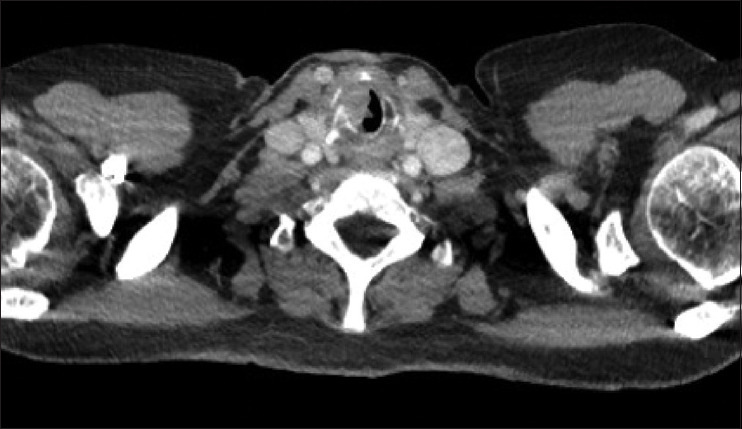

头颈癌(HNC)可在急诊科出现危及生命的症状。由于症状和体征相似,患者有时会被误诊为肺部疾病,最终导致诊断延误,并可能造成严重后果。造成这种情况的原因包括基层医疗机构和急诊科的医生对患者的风险因素缺乏认识,对疾病过程中出现的各种主诉缺乏了解。本文探讨了当代风险因素和常见症状,并讨论了对潜在头颈部恶性肿瘤患者的初步处理方法。HNC 的急诊表现多种多样,并可能与常见的呼吸系统疾病重叠。临床医生了解这一点有助于团队决定需要进行哪些适当的检查和化验,以降低延误诊断和进一步治疗的风险。

Head-and-neck cancer (HNC) can present with life.threatening symptoms in the emergency department. Patients can sometimes be misdiagnosed with pulmonary disease due to similar signs and symptoms, ultimately leading to delayed diagnosis and potentially devastating consequences. Reasons for this include lack of awareness of patient risk factors and knowledge of the myriad of presenting complaints in the disease process among physicians working in primary care and in the emergency department. This article explores the contemporary risk factors and common presenting symptoms and discusses initial management for a patient with potential head-and-neck malignancy. Emergency presentations of HNC are wide ranging and can overlap with common respiratory pathologies. Clinician awareness of this can assist the team in deciding what appropriate examination and investigations are required to reduce the risk of delaying diagnosis and further treatment.